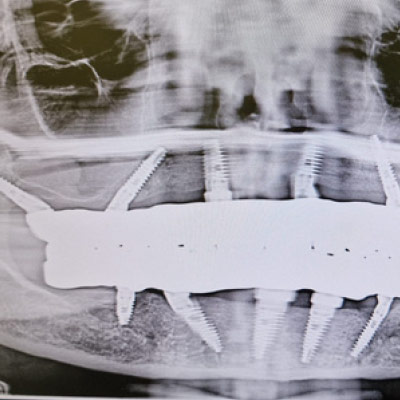

Full Arch Implant Rehabilitation

Questo corso ti prepara a gestire le riabilitazioni di una o entrambe le arcate su soli supporti implantari. Impariamo a gestire il paziente totalmente edentulo, parzialmente edentulo e quello con dentizione terminale.

All on x-procedures from A to Z.